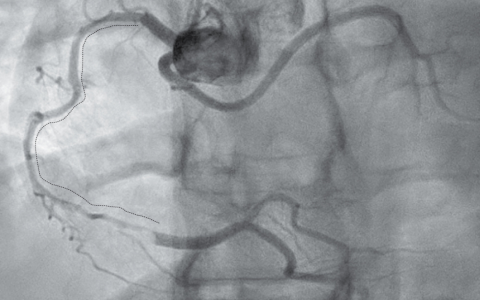

磁共振成像(MRI)显示硬脑膜强化、小脑扁桃体异位、桥前池消失以及垂体充血——这些表现均符合自发性颅内低压的特征。自发性颅内低压是一种体位性头痛,由非医源性脑脊液(CSF)漏导致脑组织下沉引起。本例中,CT脊髓造影显示在T12-L1椎间隙腹侧存在硬膜外漏(箭头所示,左下图),病因是该节段的骨赘(骨刺)。经硬膜外血贴术治疗后,患者头痛症状完全缓解。